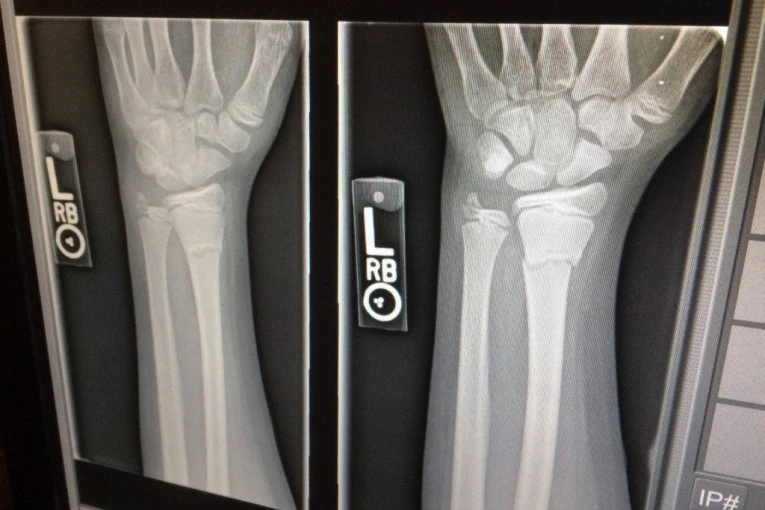

Policija je uhapsila 11 osoba, uključujući medicinsku sestru koja je povređenima davala analgetike da bi im članovi bande lomili kosti tegovima za vežbanje.